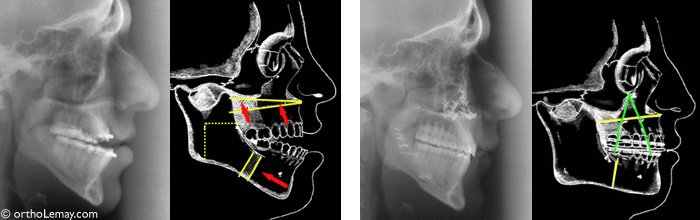

Radiographies avant et après la chirurgie et diagrammes illustrant les mouvements effectués sur les mâchoires.